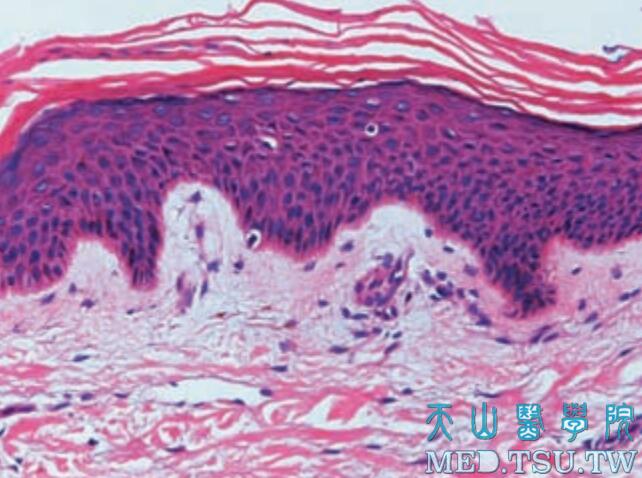

• 表皮组织:角质形成与树枝状细胞

表皮由两大类细胞所组成,即角质形成细胞与树枝状细胞。两者迥然不同,角质形成细胞具有细胞间桥以及丰富的胞质,用HE染色即可着色;而树枝状细胞则无细胞间桥,其胞质需用特殊染色或